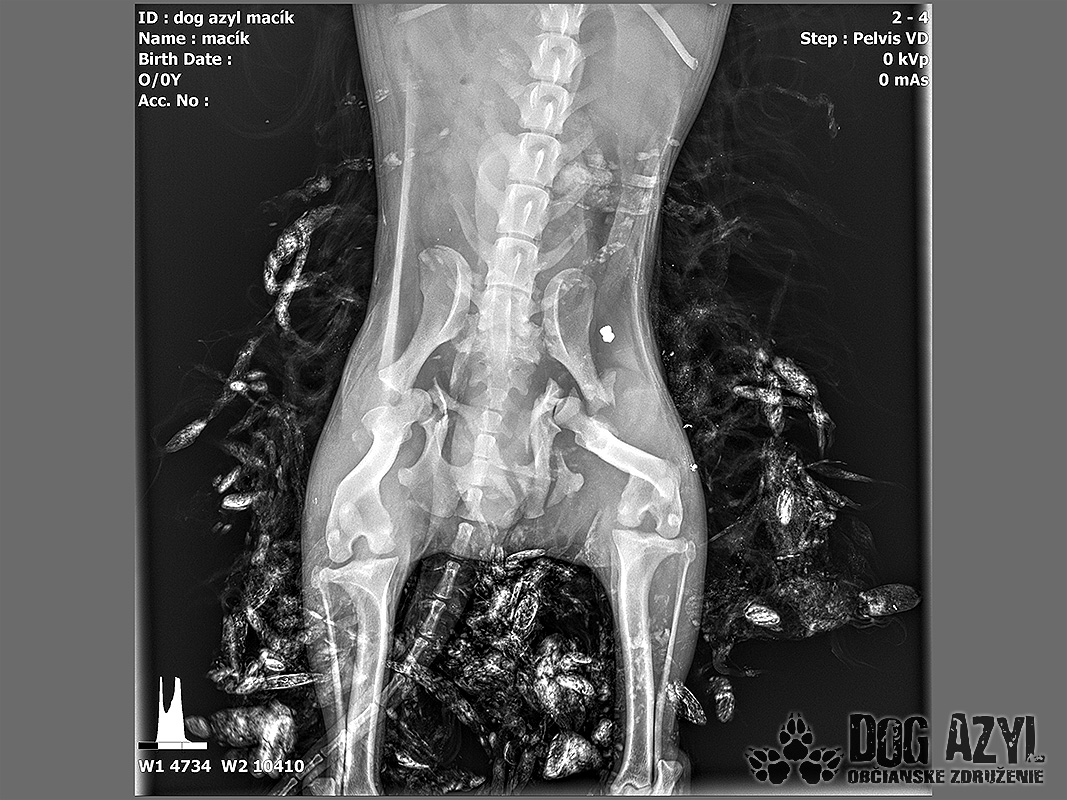

Vianoce nám klopú na dvere a mali by to byť sviatky radosti a pokoja. No u nás nebudú a pre malého Jamesa už vôbec nie. Malého Jamesa sme prijali s mnohonásobnými fraktúrami panvy. Presnejšie, s obojstrannou iliosakrálnou luxáciou/fraktúrou, viacnásobnou fraktúrou panvy, vrátane fraktúry kranialneho acetabula obojstranne. Áno, znie to hrozivo a keď si pozriete snímky z RTG, bude to ešte hrozivejšie (ďalšie snímky ešte doplníme).

Čakali ho teda štyri, veľmi náročné ortopedické operácie, takže sa musel trocha posilniť. Do starostlivosti si ho vzala MVDr. Panyi Terzieva a 17.11. mohol absolvovať prvú operáciu. V "prvom kole" krpec zvládal anestézu tak dobre, že sa rovno mohli spojiť dve operácie a tak sa celá ľavá strana dala do poriadku. Zostal samozrejme naďalej hospitalizovaný. Ďalší zákrok sa naplánoval na 20.11. a našťastie opäť všetko prebehlo hladko, a zoperovala sa celá pravá strana(nechceme sa dlho rozpisovať, prikladáme lekársku správu). James bol prepustený 24.11. ako chodiaci pacient a bez problémov ovládal aj vylučovanie! Je to priam zázrak, za ktorý opäť vďačíme MVDr. Vatolíkovi a jeho teamu.